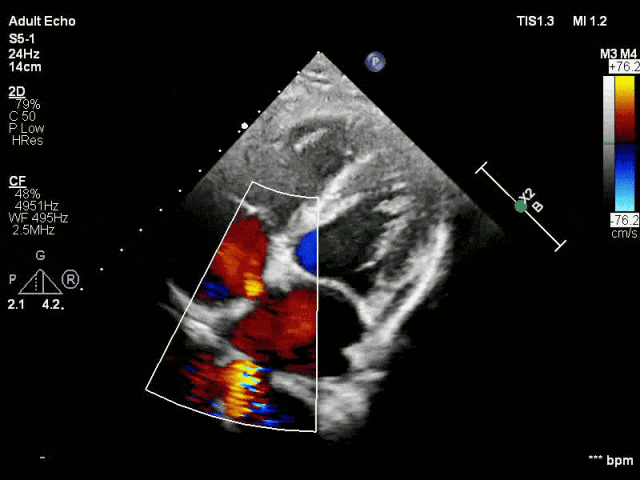

房间隔缺损介入封堵

根据术前测量结果,选择MemoSorb可降解ASD封堵器BDASD-I 14,配合14F可降解封堵器介入输送系统进行封堵。

左盘展开

右盘展开

释放后超声

超声下可见室水平和房水平都无残余分流

心脏彩超:心脏超声下可见两个封堵器双盘稳固夹持,无残余分流;

术后1个月心脏超声,房室水平皆无残余分流